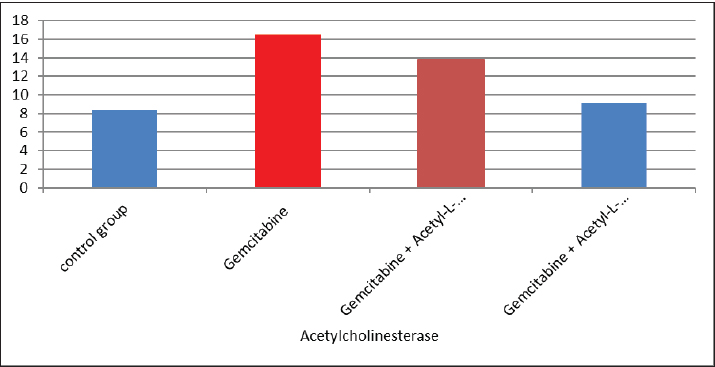

AbstractBackground: The acetyl ester of L-carnitine (ALC) is essential for cellular energy homeostasis and intermediate metabolism. It demonstrates several well-established biological characteristics, such as antioxidant activity, intracellular membrane stability, mitochondrial function improvement, and neuroprotective and neurotrophic effects. Given that oxidative stress, mitochondrial malfunction, and neuronal membrane damage have been linked to gemcitabine-induced neurotoxicity, ALC may have a preventive role against these negative consequences. Its capacity to boost mitochondrial metabolism and act as an antioxidant points to a potential mechanism for reducing damage to the central nervous system (CNS) caused by gemcitabine. Thus, using an experimental model of gemcitabine-induced neurotoxicity, we explored the possible neuroprotective benefits of ALC. Aim: This study aimed to examine the neuroprotective effects of two distinct dosages of ALC on cognitive impairment in male rats caused by gemcitabine injection. Cognitive function was assessed using well-known behavioral tests, such as the Morris water maze or novel object identification, to offer objective measures of learning and memory. This study aimed to elucidate the possible function of ALC in reducing gemcitabine-related CNS toxicity by evaluating behavioral performance in addition to biochemical indicators of oxidative stress and neuronal damage. It is anticipated that the results of this study will shed light on the dose-dependent effectiveness of ALC in maintaining cognitive function after chemotherapy. Methods: The experiment was conducted using 24 adult male rats, which were randomly assigned to four equal groups (n=6 per group). Treatments were administered once daily for 28 consecutive days. Group 1 (G1–Control): Rats received a subcutaneous injection of normal saline and served as the negative control. Group 2 (G2–Gemcitabine 25 mg/kg): Rats received 25 mg/kg of Gemcitabine intraperitoneally once daily. Group 3 (G3– ALC 50 mg/kg): Rats received 50 mg/kg of ALC intraperitoneally once daily. Group 4 (G4–Gemcitabine + ALC): Rats received a combination of Gemcitabine (25 mg/kg bw) and ALC (50 mg/kg bw), both administered intraperitoneally once daily. All treatments were administered at the same time each day to ensure consistency, and the animals were monitored throughout the study period to assess their health status and minimize stress. Results: Rats receiving ALC in addition to gemcitabine demonstrated a significant reduction in gemcitabine-induced adverse effects (p < 0.05) compared with the group treated with gemcitabine alone. This protective effect was mainly seen in characteristics associated with the function of the central nervous system, that ALC plays a neuroprotective role. Conclusion: The fourth experimental group (G4) had considerably lower levels of β-amyloid and acetylcholinesterase activity than the second (G2) and third (G3) groups. Furthermore, brain sections from the G4 group showed significantly fewer β-amyloid plaques than those from the G2 and G3 groups, according to Congo red staining histological analysis. Keywords: Acetyl-L-carnitine, Acetylcholinesterase, Beta amyloid, Congo red, Gemcitabine. IntroductionCancer treatment is frequently associated with adverse effects, as the toxicity of chemotherapeutic agents can reduce life expectancy and significantly impair patients’ quality of life. Gemcitabine is a potent cytotoxic antimetabolite that is widely used for treating various solid tumors, including pancreatic, lung, breast, and bladder cancers. Gemcitabine primarily exerts its anticancer effects by inhibiting DNA synthesis during the S phase of the cell cycle. Accurate depiction of medication indications and mechanisms of action is crucial, even though chemotherapy-induced toxicity is a significant therapeutic problem. Thus, the toxicological effects of gemcitabine administration are the main topic of this investigation, with a focus on the systemic effects (Maleki et al., 2025). White blood cell malignancies, including non-Hodgkin lymphoma, acute myeloid leukemia, also known as acute lymphocytic leukemia, and long-term myelogenous leukemia, are the main conditions treated with gemcitabine, a class of chemotherapeutic medication (Larson et al., 2024). Its effects are specific to the S-shaped cellular cycle. Significant chromosomal damage causes chromosomal abnormalities. Mitosis has the greatest effect in cells with rapid division that need to duplicate DNA (Yi et al., 2022) reactive oxygen species (ROS) are produced, and their concentrations are decreased because the function of enzymes known as antioxidants in the liver tissues is inhibited by gemcitabine. However, since this combination is known to undergo significant hepatic metabolism, the resulting increase in ROS may contribute to brain tissue injury (Tauffenberger and Magistretti, 2021). The liver, kidney, and brain all naturally produce the amino acid L- alongside the necessary amino acids methionine and lysine (Davidova et al., 2022). Since the chemical originates after flesh, its scientific designation is derived from the Latin carnus, which means meat Taub (2023). Acetyl-L-carnitine (ALC) is essential for energy utilization because it moves toxic compounds through organelles and prevents these contaminants from building up inside the cell’s tissues. It additionally carries long-chain fatty acids to the mitochondria Javan et al. (2025). ALC is essential for the oxidation of fatty acids and the conversion of energy; thus, it might safeguard the cell membranes from damage caused by oxidative stress (Kıran et al., 2023). ALC might inhibit these chemical reactions in cells by numerous pathways—preservation of mitochondrial function (Huseynova, 2025) and reduction of ROS generation at various intracellular sites (Virmani and Cirulli, 2022). Protein Kinase B is among the most common neurotransmitters in the human nervous system. Ace is a neurotransmitter used as a signaling molecule by neurons with cholinergic activity (Zulfugarova et al., 2025). The activity of cholinesterase is crucial to stop chemicals released from acetylcholine neurons from reaching the nervous system, skeletal muscle, or gland that is being activated (Ashraf, 2023). Acetylcholinesterase (AChE) quickly breaks down acetylcholine into choline and acetic acid, rendering it ineffective. The brain’s nervous system needs oxygen to function properly (Guliyeva et al., 2025). Because ace is inhibited, acetylcholine can accumulate, overstimulating cholinergic junctions and organs controlled by cholinergic neurons (Lakshmanan, 2021). Materials and MethodsIn this study, 24 male white albino rats weighing between 260 and 300 g were used. Individuals were housed in well-maintained cardboard cages that included proper ventilation, light structure, and temperature (about 30℃ ± 5℃) for 12 hours each day. The trial was conducted during a 28-day period. Twenty-four adult male rats were randomly divided into four experimental groups, each consisting of six animals. Six male rats in Group I (G1, control group) were administered intraperitoneal injections of normal saline once a day during the experiment. Six male rats in Group II (G2) received 25 mg/kg body weight of intraperitoneal gemcitabine. Six male rats in Group III (G3) were administered intraperitoneal doses of gemcitabine (25 mg/kg body weight) and ALC (50 mg/kg body weight). Six male rats in Group IV (G4) were administered gemcitabine (25 mg/kg body weight) and ALC (50 mg/kg body weight) intraperitoneally for 4 consecutive days. Blood samples were taken from each rat separately and appropriately labeled to prevent sampling bias. In compliance with institutional ethical guidelines for animal care and use, the animals were put to sleep before blood collection using a compassionate and authorized anesthetic approach instead of being exposed to chloroform. Blood was drawn via heart puncture using sterile needles in an aseptic setting after anesthesia was administered. Each animal provided approximately 5 ml of blood. The leftover blood was split into two parts, and 1 ml was set aside for whole blood analysis. After transferring approximately 2 ml into gel tubes, the mixture was left to coagulate for 30 minutes at room temperature. Study parametersMeasurement of serum β-Amyloid (Aβ₁–₄₂) A commercial rat ELISA kit (Elabscience Biotechnology Comapny Ltd., China) was used to measure serum β-amyloid (Aβ₁–₄₂) concentrations according to the manufacturer’s instructions. A quantitative sandwich enzyme immunoassay method serves as the foundation of the assay. Results were expressed in pg/ml, and the sensitivity and detection range of the kit were within the manufacturer’s limits. Every sample was examined twice to guarantee analytical precision and repeatability. Serum AChE measurementA rat AChE enzyme-linked immunosorbent assay kit (Elabscience Biotechnology Company Ltd., China) was used to test serum AChE levels in accordance with the manufacturer’s instructions. A microplate reader was used to detect the absorbance, and the standard calibration curve was used to determine the concentrations. The kit’s stated units were used to express the results. Every measurement was conducted twice, and assay performance was verified using the manufacturer’s quality control methods. Histopathological analysis (Congo red staining)Brain tissues were quickly removed and preserved for 24–48 hours following animal sacrifice in 10% neutral buffered formalin. Samples were dehydrated, cleaned, and embedded in paraffin following conventional histological methods. To find β-amyloid buildup, coronal slices (4–5 µm thick) were taken and stained with Congo red. The hippocampus and cerebral cortex, two brain areas linked to cognitive performance, were histologically examined. An investigator who was blinded to the experimental groups examined the amyloid deposits under light microscopy. Statistical analysisSPSS software (version 24.0; IBM Corp., USA) was used to analyze the data. Every outcome is presented as mean ± standard error. One-way analysis of variance was used to compare the various experimental groups. When a statistically significant difference was found, Tukey’s test was used in post-hoc multiple comparison analysis to find differences between individual groups. A statistically significant p-value was defined as <0.05. Ethical approvalThis work was approved by the ethics committee of the College of Veterinary Medicine, Kerbala University (UOK.VET. PH.2025). ResultsThe results of the present investigation indicate that the Gemcitabine group had a significant (p ≤ 0.05) raised level of blood samples beta-amyloid when compared with the remainder of the categories, whereas the Gemcitabine + ALC (25 mg/kg/bw) group showed a significant (p ≤ 0.05) improve when contrasted to the comparison group and the combination of Gemcitabine + ALC (300 mg/kg/bw) organization. However, Fig. 1 shows that there was no statistically significant difference (p > 0.05) in serum-amyloid levels between the control group and the group treated with gemcitabine + ALC (300 mg/kg bw). The present research also demonstrates that the Gemcitabine category had a significant (p ≤ 0.05) improvement in blood samples AChE when compared with each of the remaining organizations, whereas the gemcitabine + ALC (25 mg/kg/bw) category showed an important (p ≤ 0.05) increase when compared with the group that received no treatment and the gemcitabine + ALC (300 mg/kg/bw) organization (Fig. 1).

Fig. 1. Effect of gemcitabine, gemcitabine + ALC (25 mg/kg/bw), and gemcitabine + acetyl-L-incarnadine (300 mg/kg/bw) on serum beta-amyloid levels. The present research also demonstrates that the Gemcitabine category had a significant (p ≤ 0.05) improvement in blood samples AChE when compared with each of the remaining organizations, whereas the gemcitabine + ALC (25 mg/kg/bw) category showed an important (p ≤ 0.05) increase when compared with the group that received no treatment and the gemcitabine + ALC (300 mg/kg/bw) organization (Fig. 2).

Fig. 2. Effect of gemcitabine, gemcitabine + ALC (25 mg/kg/bw), and gemcitabine + ALC (300 mg/kg/bw) on serum AChE. Histological resultsAccording to the histological investigation, the central nervous system did not contain any beta clusters. The experimental beta-amyloid turns red because it is stained using the pigment Congo red, indicating that the central nervous system is secure from beta-amyloid buildup in the absence of treatment (Fig. 3). The gemcitabine group showed an increase in beta-amyloid accumulation in the rat’s brain, which is stained in red color as shown in Figure 4. However, compared to the gemcitabine group, rats administered gemcitabine plus ALC (25 mg/kg/bw) showed a significant reduction in the buildup of beta-amyloid in the rat’s brain, as depicted in Figure 5. Furthermore, as illustrated in Figure 6, rats treated with gemcitabine + ALC (300 mg/kg/bw) exhibit a significant reduction in the buildup of beta-amyloid in their brains when compared to rats treated with gemcitabine + ALC (25 mg/kg/bw).